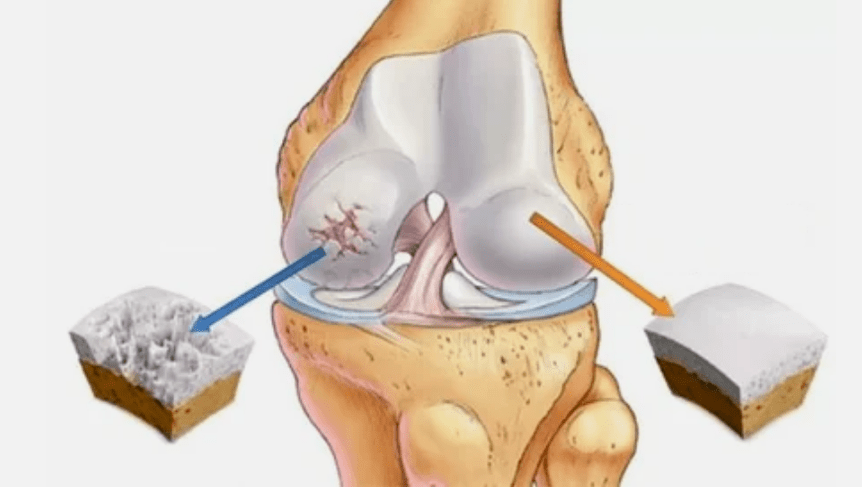

- Die Primärverletzung wirkt sich auf die Knorpel ialina aus. Bei Kreislaufstörungen tritt eine Verschlechterung der pathologischen Kraft auf. Es ist der erste Schritt oder die erste Ursache, die Arthrose auftreten kann.

- IALINA -Beschichtungspathologien. Die Ausdünnung des Knorpels führt zum Ersatz seiner pathologischen Gewebe - Knochenstrukturen.

- Die anomalen Wachstum erscheinen auf Knorpel - Osteophyten.

- Die Verletzung der natürlichen Anatomie von Knorpel und Knochen verursacht die Überlastung gesunder Knorpelbereiche. Die Zerstörung von gemeinsamen Geweben ohne Behandlung führt ständig voran und führt zu Behinderungen.

Wenn der Krankheitsgrad zunimmt, sind pathologische Prozesse immer noch verschlimmert. Am Ende wird der gesamte Knorpel Ialina zerstört.

- Reduzieren Sie die Lücke in die Lücke des Gelenks, die auf dem Foto deutlich wird. Das Stadium des Verstoßes wird vom diagnostisch-Anthgenologen bestimmt. Der Patient spürt die Komplexität oder Unfähigkeit, das Glied zu begradigen und vollständig zu falten.

- Gelenkverformung, der Knorpel erhält eine unregelmäßige Form, die Krümmung verursacht;